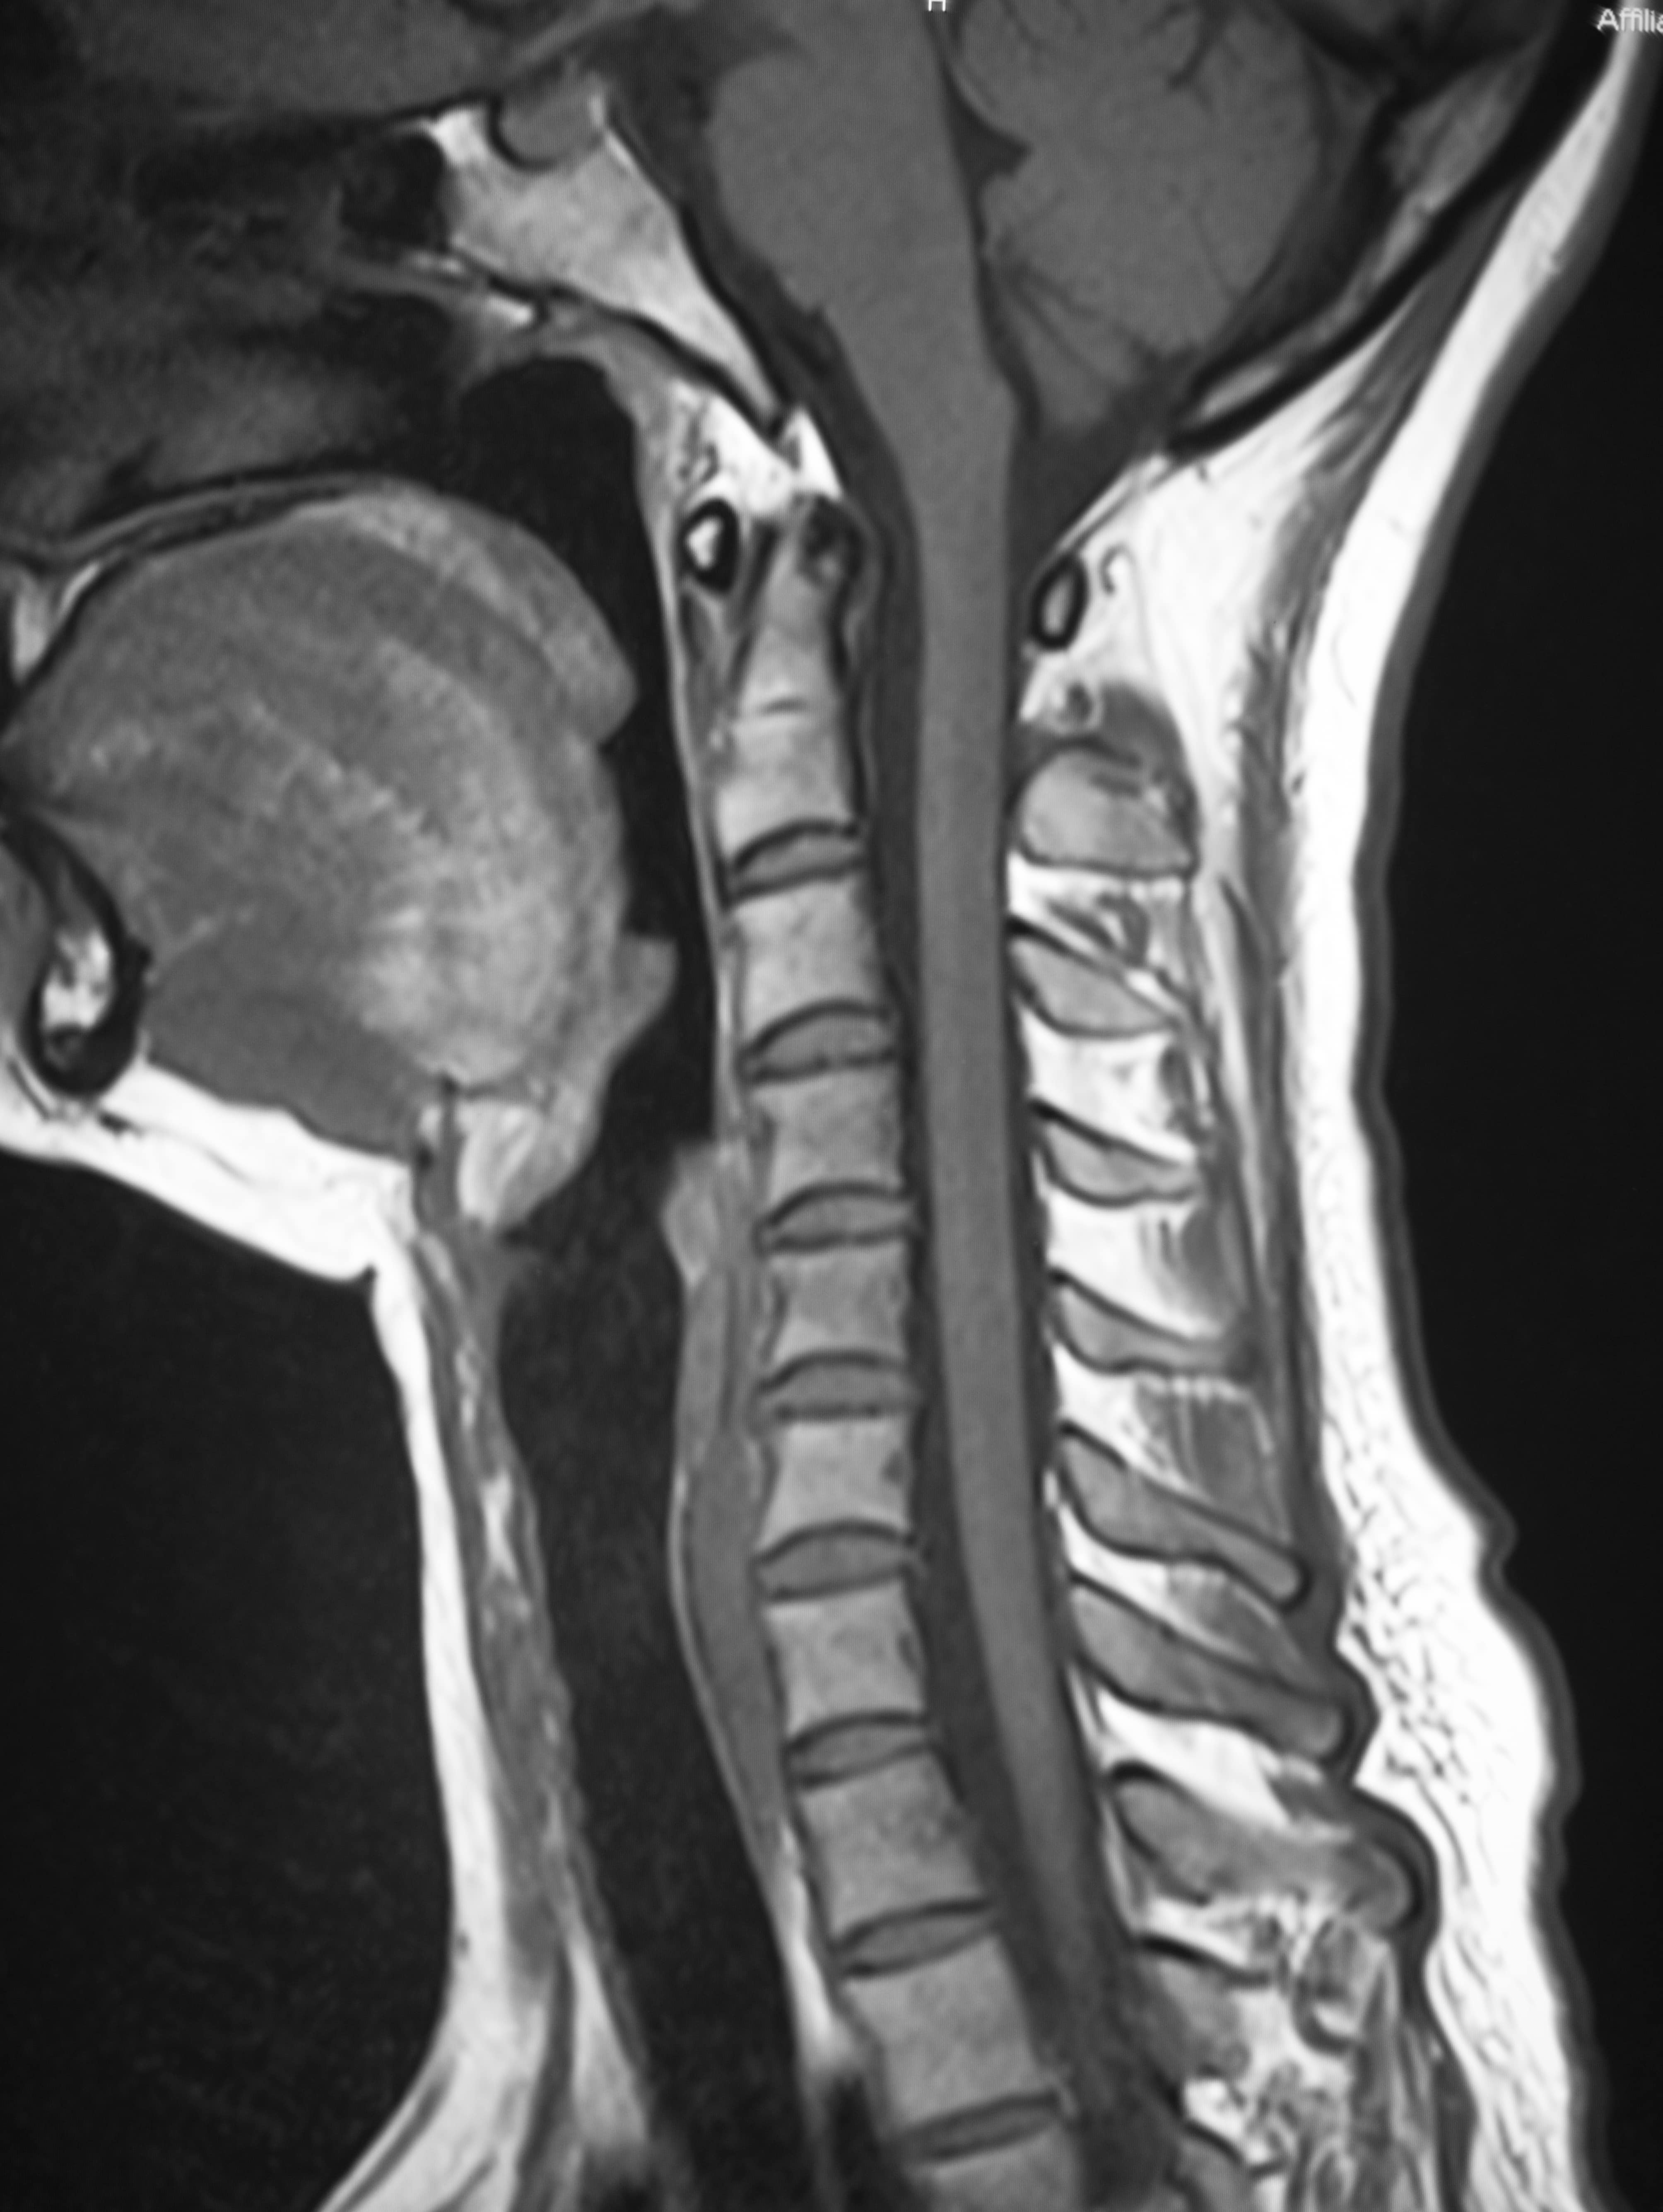

Image Results

Cervical Spinal Stenosis